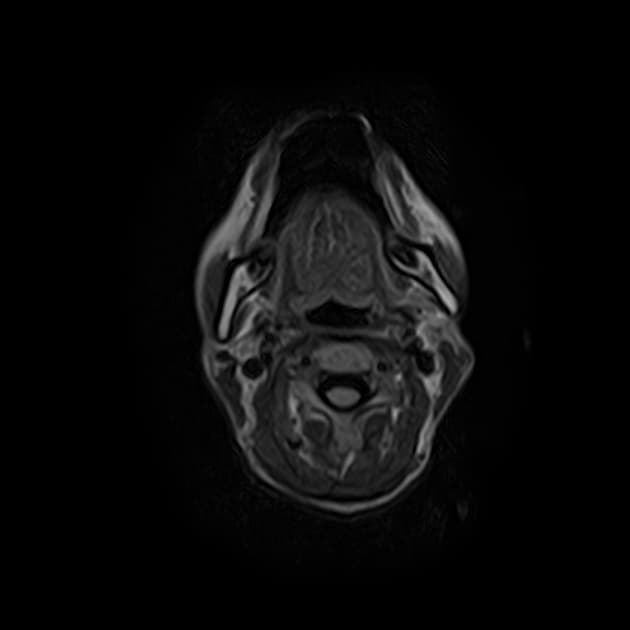

Chụp cộng hưởng từ (MRI) cho thấy các đặc điểm điển hình của bệnh xơ cứng rải rác. Ngoài ra, một số tổn thương có tín hiệu tăng trên hình ảnh T1 (T1 hyperintense).

Các phát hiện chính:

- Các tổn thương rải rác, dạng vệt hoặc hình tròn, tăng tín hiệu trên hình ảnh khuếch tán (diffusion-weighted imaging), khu trú chủ yếu ở vùng chất trắng quanh thất (periventricular white matter), chất trắng ở bán nguyệt (juxtacortical white matter), thân gai thị – giao thoa thị giác (optic radiation – optic chiasm), và thân não (brainstem) – phù hợp với đặc điểm của xơ cứng rải rác (multiple sclerosis).

- Một số tổn thương có tín hiệu tăng trên T1 (T1 hyperintense lesions) – gợi ý tổn thương mạn tính, liên quan đến mức độ tàn phế tăng và teo não (atrophy).

- Không có bằng chứng của phù độc tế bào (cytotoxic edema) cấp tính hay hạn chế khuếch tán (restricted diffusion) mới.